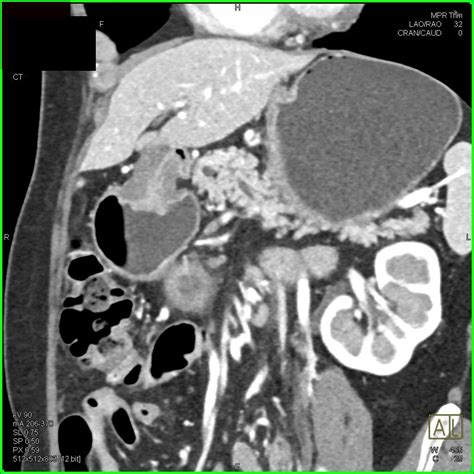

• Imaging Tests: Such as ultrasound, CT scan, or MRI to visualize the pancreas and its ducts.